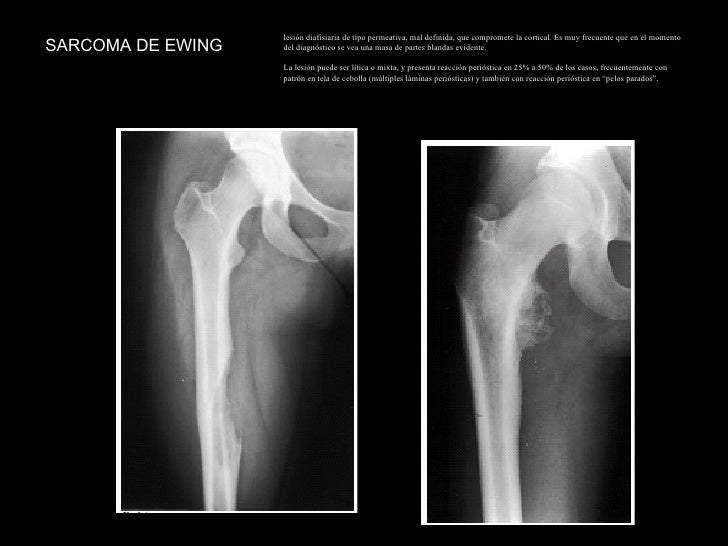

Tumores oseos ewing sarcoma reaccion. Ewing sarcoma bone tumor humpath gross femoral pathology cavity webpathology medullary defined thickening cortical ill specimen frequently expanding mass showing

Ewing sarcoma bone tumor humpath gross femoral pathology cavity webpathology medullary defined thickening cortical ill specimen frequently expanding mass showing. Tumores oseos ewing sarcoma reaccion